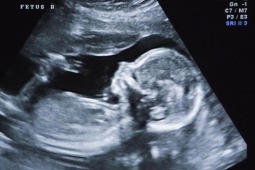

W Hongkongu przyszła na świat dziewczynka, u której w jamie brzusznej jeszcze w życiu płodowym lekarze odkryli resztki dwóch innych płodów, jej rodzeństwa. Okazało się, że nie jest to przypadek tzw. potworniaka, który na początku podejrzewano.

"Lekarze stwierdzili jednak, że jest to wyjątkowo rzadki przypadek nazywany "płodem w płodzie", który zdarza się raz na 500 tys. narodzin. Polega on na tym, że we wczesnym okresie życia płodowego rozwija się kilka zarodków, ale w pewnym momencie jeden z nich wchłania pozostałe, które obumierają" - informuje "Hongkong Medical Journal".

W organizmie kobiety, która urodziła dziewczynkę z resztkami dwóch innych płodów, początkowo rozwijały się trzy zarodki. Po kilku tygodniach ciąży dwa z nich zostały wchłonięte przez płód żeński. Początkowo lekarze ze szpitala Św. Elżbiety w Hongkongu sądzili, że w organizmie płodu rozwija się sporych rozmiarów guz. Postanowili przeprowadzić operację jeszcze w łonie matki, żeby go usunąć.

Wtedy dopiero chirurdzy odkryli, że w jamie brzusznej płodu, między wątroby a nerką, są obumarłe już dwa inne zarodki.

- Jeden miał 9,3 g, a drugi – 14,2 g i własne łożyska – powiedział dr Nicholas Chao, jeden z przeprowadzających operację chirurgów.

Obydwa płody zatrzymały się w rozwoju między 8. i 10. tygodniem ciąży. Zdążyły się u nich wytworzyć kończyny, klatka piersiowa, skóra i jelita oraz zapoczątkowany został rozwój mózgu.